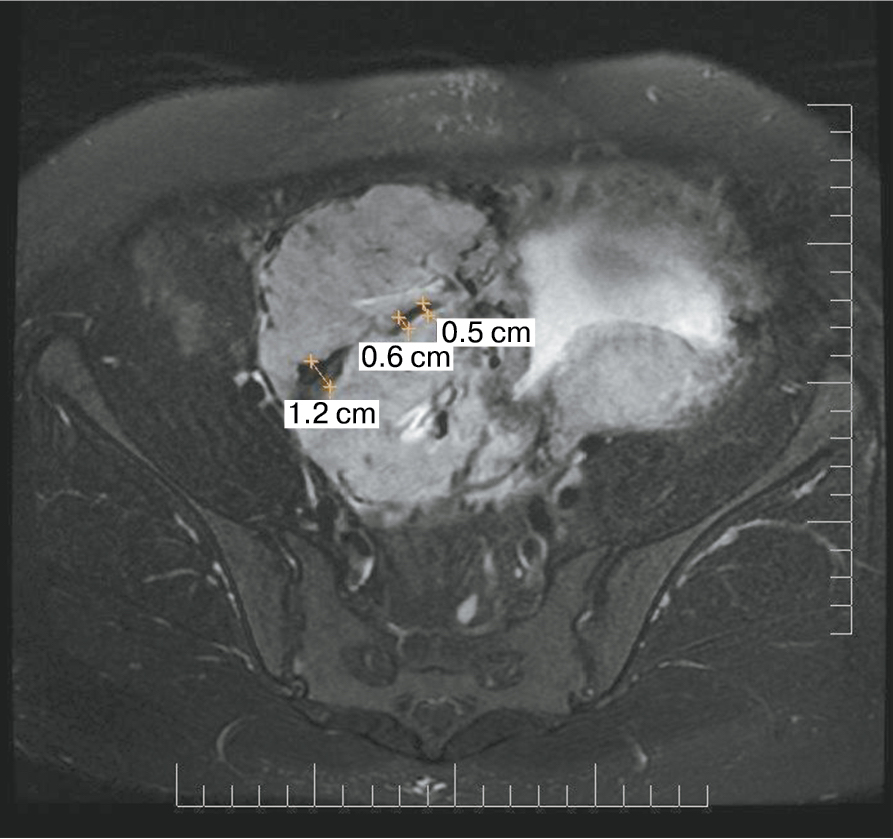

Также стоит выделить особый тип плацентарной гиперваскуляризации, а именно включение в плацентарной ткани изменений по типу «обнаженного сосуда» (рис. 1, 2). Мы провели анализ встречаемости данного признака среди наших пациентов. Любопытным наблюдением явилось то, что данный симптом в нашей выборке встречался только при наличии placenta percreta – 6 случаев, а именно при поражении параметриев, и не встречался при плацентарной инвазии, ограниченной миометрием. «Мостовидные сосуды» были менее специфичны, тем не менее, их наличие также сопровождало тяжелые формы врастания, обусловленные более глубокой инвазией ворсин хориона, – 8 случаев.

Рис. 1. МРТ placenta percreta, симптом «обнаженного сосуда»

Рис. 2. МРТ placenta percreta, симптом «обнаженного сосуда»

Является ли симптом «обнаженного сосуда» патогномоничным для параметральной инвазии или нет, еще предстоит выяснить; однако в ходе исследования установлена его связь с частотой гистерэктомий в группах с наличием симптома «обнаженного сосуда», что, вероятно, обусловлено мощной сосудистой сетью коллатералей и неоангиогенезом. Во всех случаях обнаружения данного признака впоследствии была выполнена вынужденная гистерэктомия (рис. 3–6, пациентка Н., 37 лет).

Рис. 5. Корональная проекция МРТ. 1 – интрамуральная гиперваскуляризация; 2- измененный контур мочевого пузыря

Рис. 6. Корональная проекция МРТ. 1 – обнаженный сосуд; 2 – интрамуральная гиперваскуляризация; 3 – гиперваскуляризация плаценты